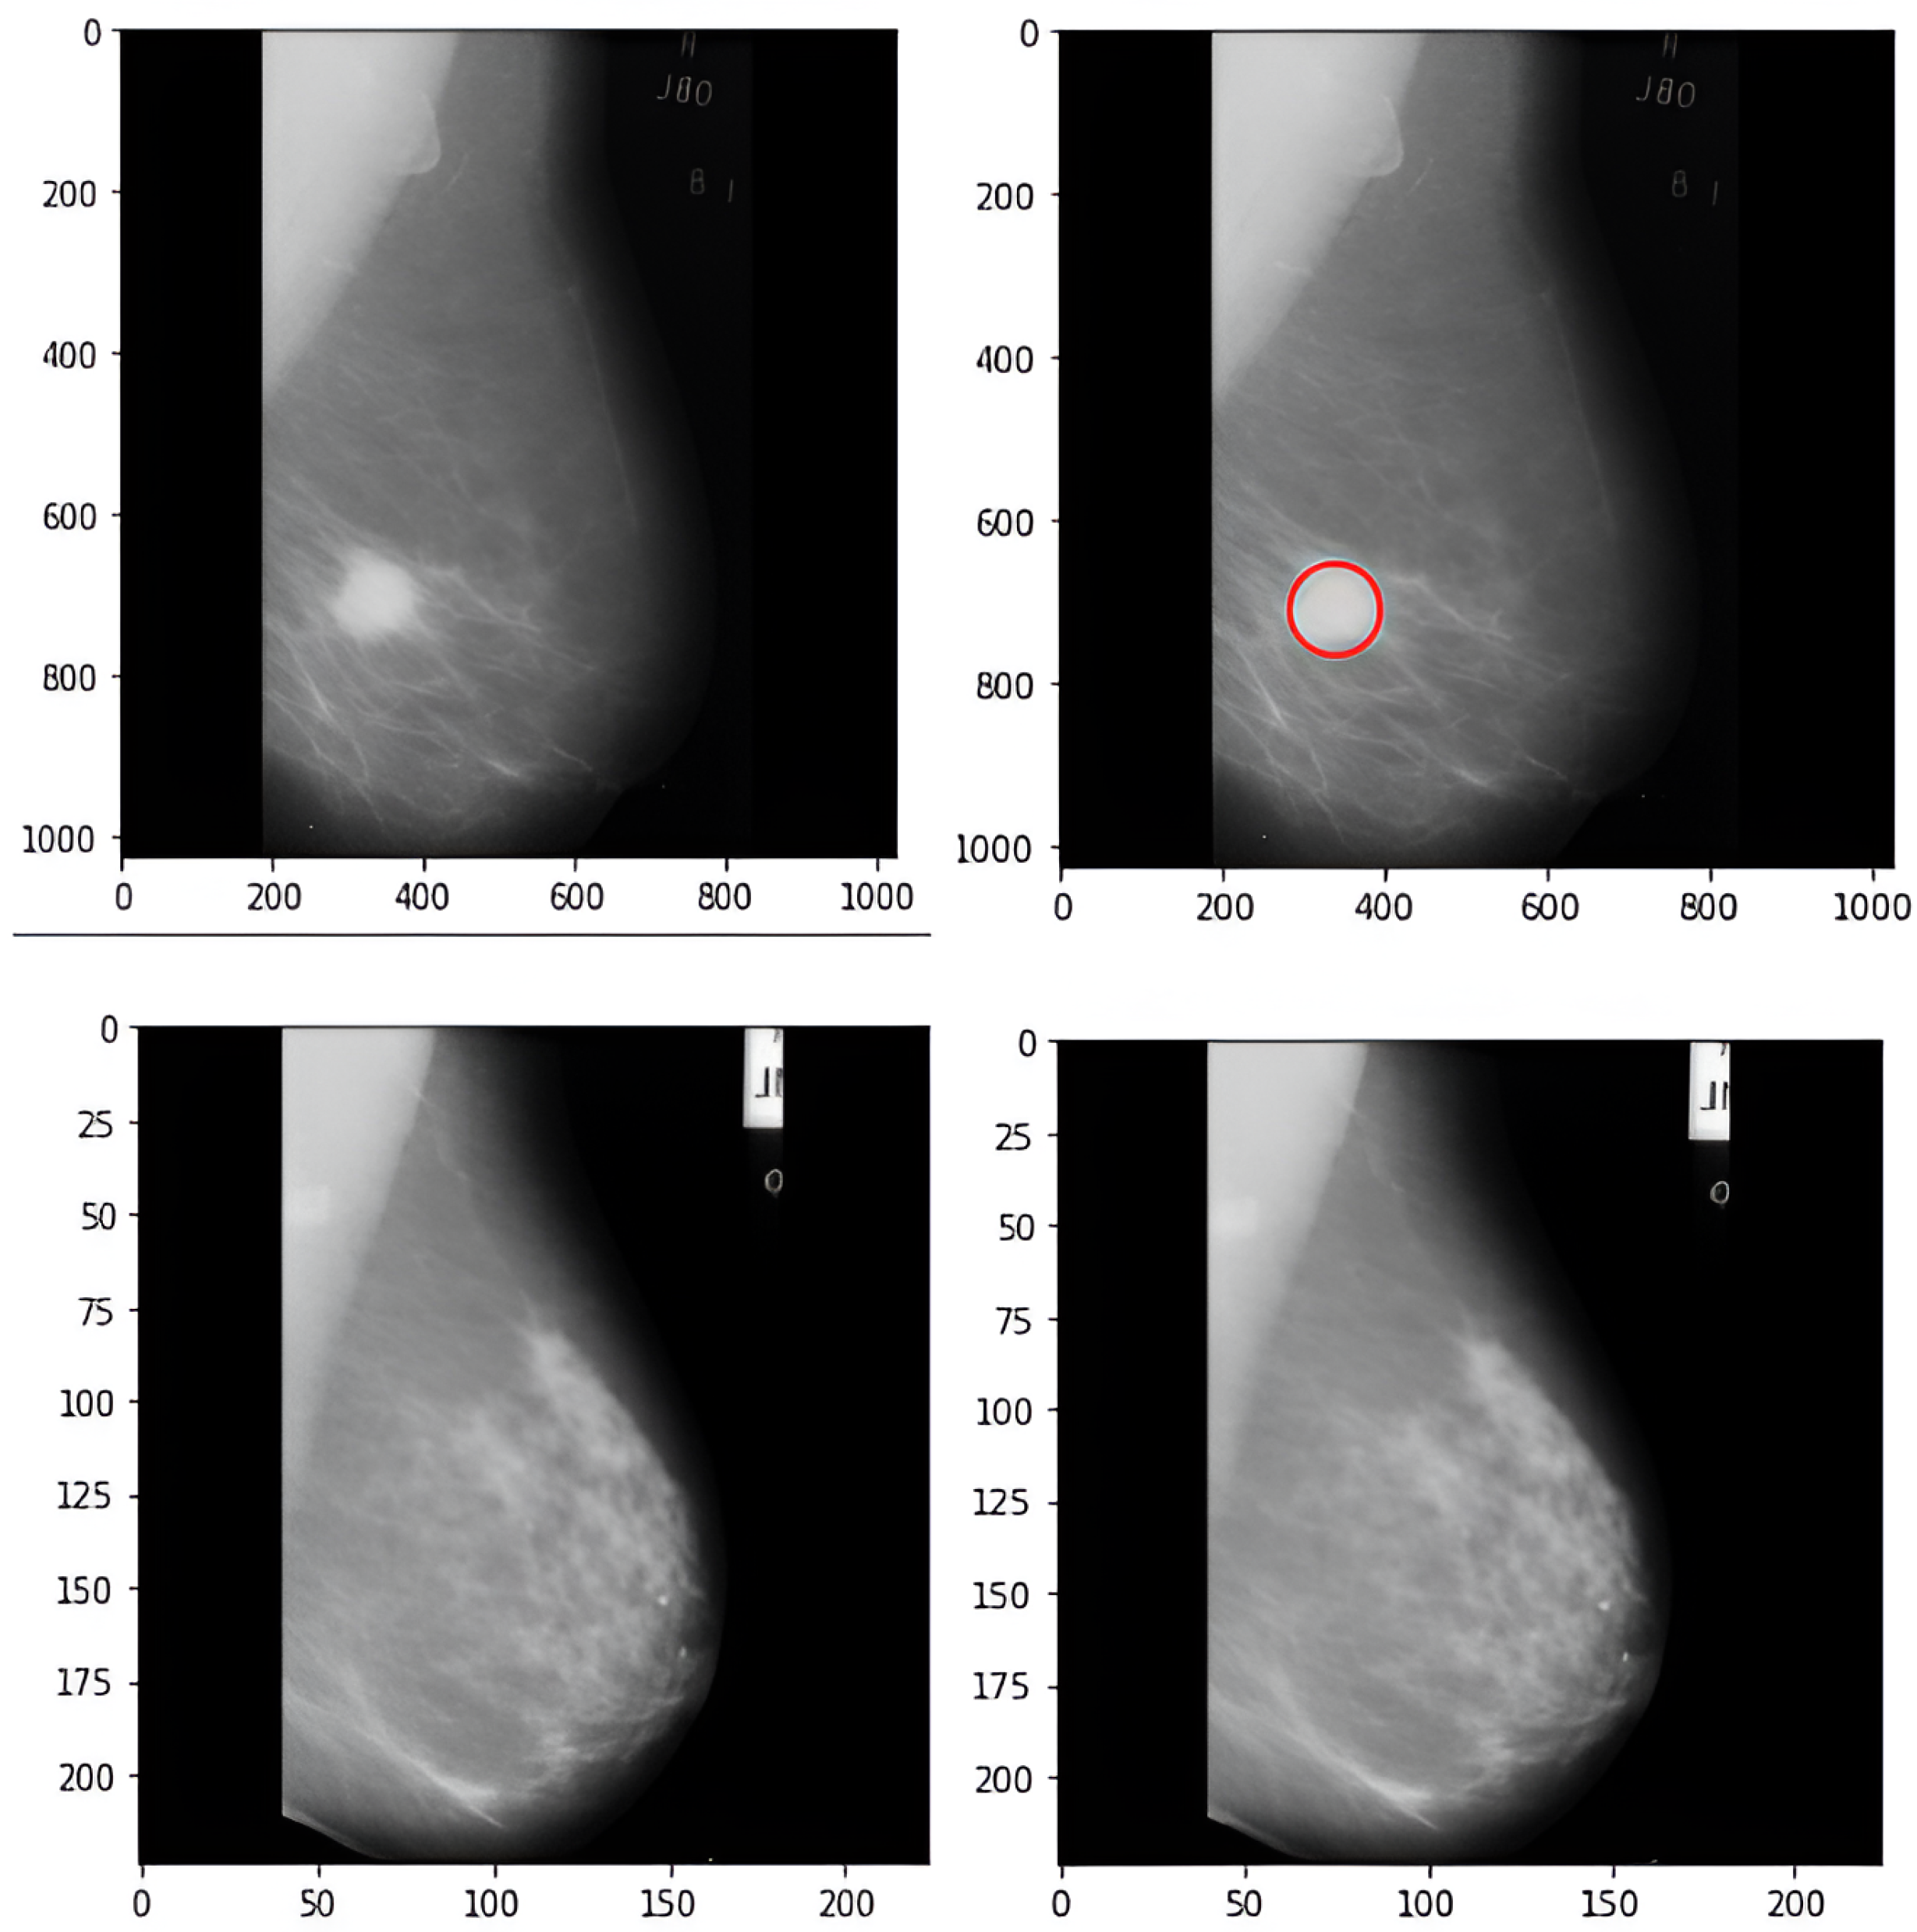

3.1. Dataset and Preprocessing